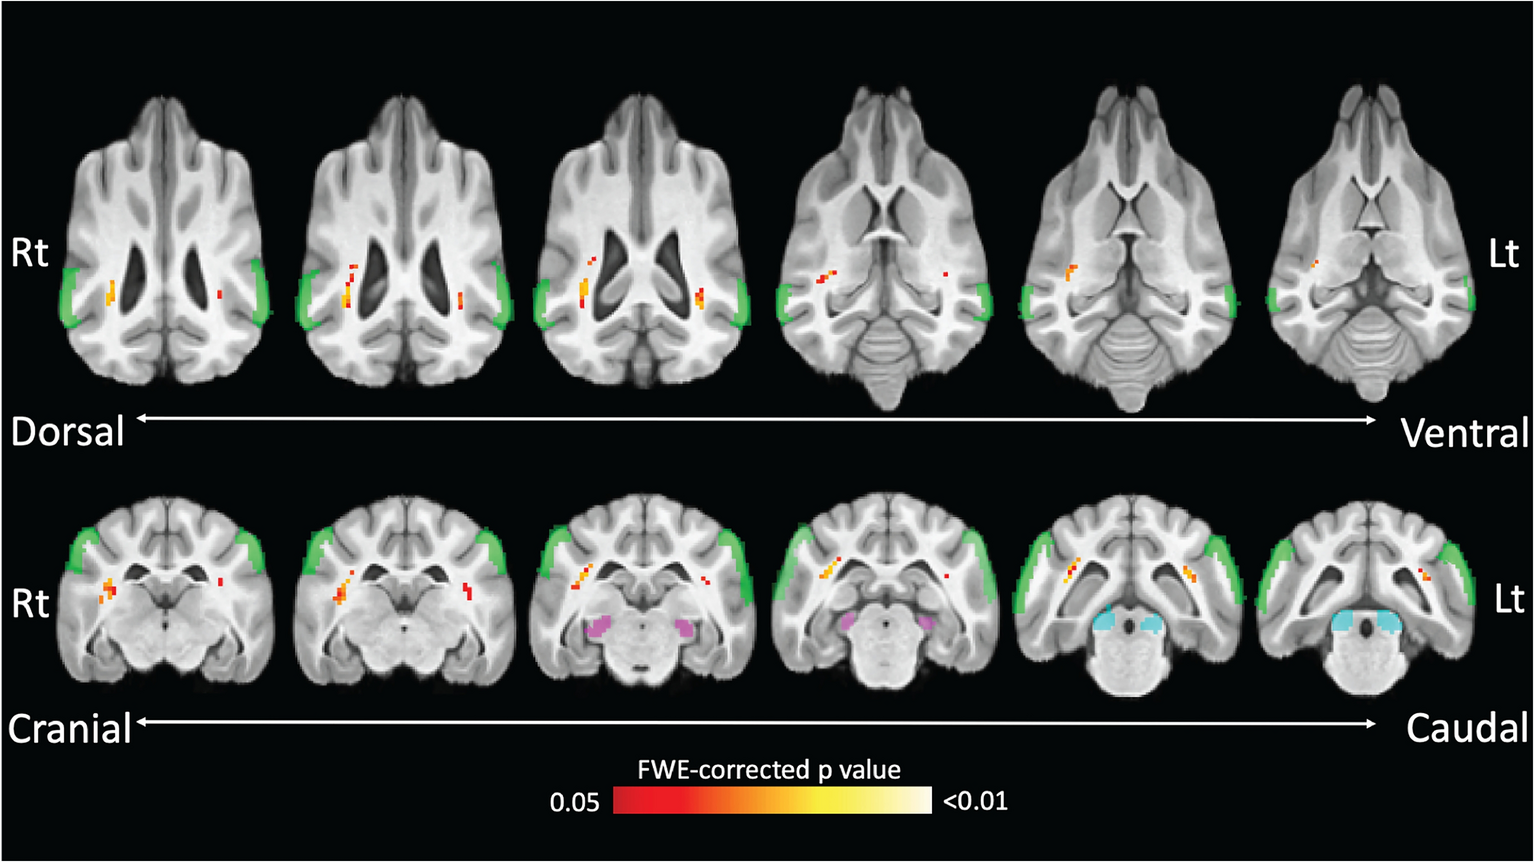

Figure 5

Heatmap visualization of TBSS results overlaid on a brain atlas. This heatmap highlights voxels with a significant negative correlation between FA and FLS. The color gradient from red to white reflects a spectrum of FWE-corrected p values. The green regions correspond to the ectosylvian cortex, the purple regions correspond to the medial geniculate nucleus, and the blue regions correspond to the caudal colliculus.